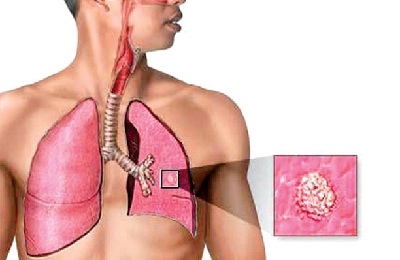

Классический вариант развития заболевания у взрослых и детей — легочная форма, характеризующаяся скоплением микобактерий (МБТ) с образованием туберкулем. Данные изменения регистрируются при помощи рентгена.

Туберкулезная интоксикация в большей степени определяет общую реакцию организма на внедрение микобактерий. Подобный вариант, а также туберкулезное поражение ВГЛУ (внутригрудных лимфатических узлов) и первичный туберкулезный комплекс (ПТК) распространен у детей и подростков. Для постановки диагноза пульмонологам требуются лабораторные исследования, положительная реакция диагностических тестов (проба Манту, диаскинтест), данные осмотра и анамнеза в сочетании с отсутствием специфических изменений в легких по данным флюорографии или рентгенографии.

При первом контакте с палочкой Коха в 5% случаев возможно развитие туберкулезной интоксикация у детей и подростков. Источником инфицирования первичной формы туберкулеза является человек с открытым вариантом инфекции, когда каверна связана с дренирующим бронхом. В таком случае во время разговора, кашле МБТ попадают в окружающую среду.

Затем при вдыхании зараженного воздуха палочки Коха оказываются в легких, но специфических туберкулезных изменений не возникает. Они мигрируют в лимфатические узлы, где уже провоцируют воспаление. Далее отмечается массивное распространение по всему организму с формированием признаков отравления с учетом особенностей туберкулеза.

Бактерии, вызывающие заболевание, попадают в организм чаще всего аэрогенно, реже – через ЖКТ или при тактильном контакте. Задерживаются и размножаются они в альвеолах – нижней части дыхательного аппарата, по виду напоминающего пузырьки.

Некоторые бактерии попадают в лимфу и кровь, а с током этих жидкостей – в органы, где много макрофагов – клеток, отвечающих за уничтожение чужеродных и токсичных частиц в организме человека.

Первичный туберкулез локализуется, как правило, в лимфатических узлах и легких, реже – в почках, суставах, брюшной области, костной ткани.

Деятельность микобактерий в организме провоцирует его на иммунный ответ в виде формирования особого клеточного иммунитета. При неправильном балансе реакций возникает избыточное производство веществ, повреждающих клеточные мембраны и вызывающих нарушение метаболизма в клетках. В результате вырабатываются токсины, которые с током крови разносятся по органам и вызывают интоксикационный синдром, являющийся признаком первичного туберкулеза.

Если лечение не проводится, интоксикация может стать хронической. При прогрессировании заболевания микобактерии поражают лимфатическую систему, попадая во внутригрудные отделы. Далее туберкулез переходит и в другие лимфоузлы, их поражает частичный или тотальный казеоз, который охватывает окружающие клетки, сосуды и бронхи.

Такая форма получила название туберкулеза внутригрудных лимфатических узлов, она наиболее распространена среди зарегистрированных форм первичного туберкулеза.

Вследствие естественного тока лимфы болезнь редко распространяется за пределы бронхов и не затрагивает легкие. По мере прогрессирования воспаления лимфоидная ткань превращается в грануляции и, увеличиваясь, способна распространиться почти на весь лимфоузел. Локальное поражение может быть значительным.